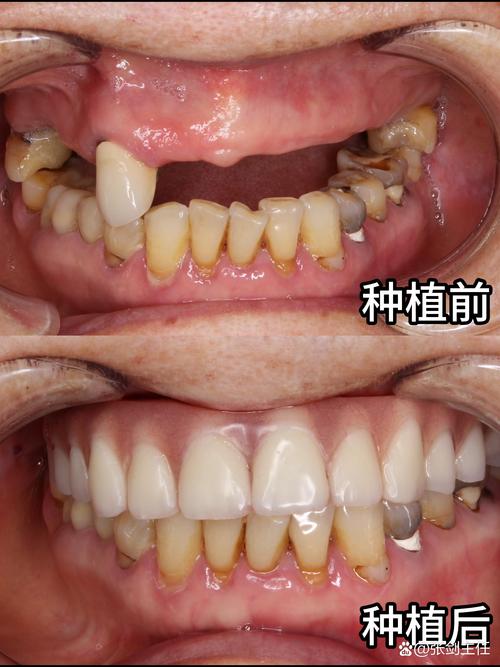

尽管种植牙初期投入较高,但从长期来看,其性价比远高于活动假牙、固定桥等传统修复方式,活动假牙需磨损邻牙,且易导致食物嵌塞、口腔黏膜损伤,使用寿命约5-8年;固定桥需磨除健康邻牙,可能导致邻牙受损,使用寿命约10-15年;而种植牙不损伤邻牙,咀嚼效率高达90%以上(接近天然牙),若维护得当,使用寿命可长达20-30年,甚至终身,种植牙能有效防止牙槽骨萎缩——缺牙后牙槽骨会因失去咀嚼刺激而逐渐吸收,导致面部塌陷、显老,而种植体的“仿生牙根”功能可刺激骨组织,维持口腔健康,从“终身使用”和“生活质量”的角度看,种植牙的“高费用”实为一项值得的健康投资。